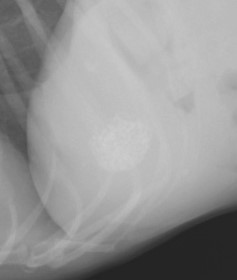

胆石が存在しているだけであれば症状が出ないことも多いですが、胆石が詰まってしまうと、胆汁の流れが悪くなり(胆管閉塞感による胆汁うっ滞)、黄疸を生じ、ひどい場合には胆嚢が破裂してしまうこともあります。

胆石の詰まる場所によっても異なりますが、手術による摘出が必要となってしまうことが一般的です。